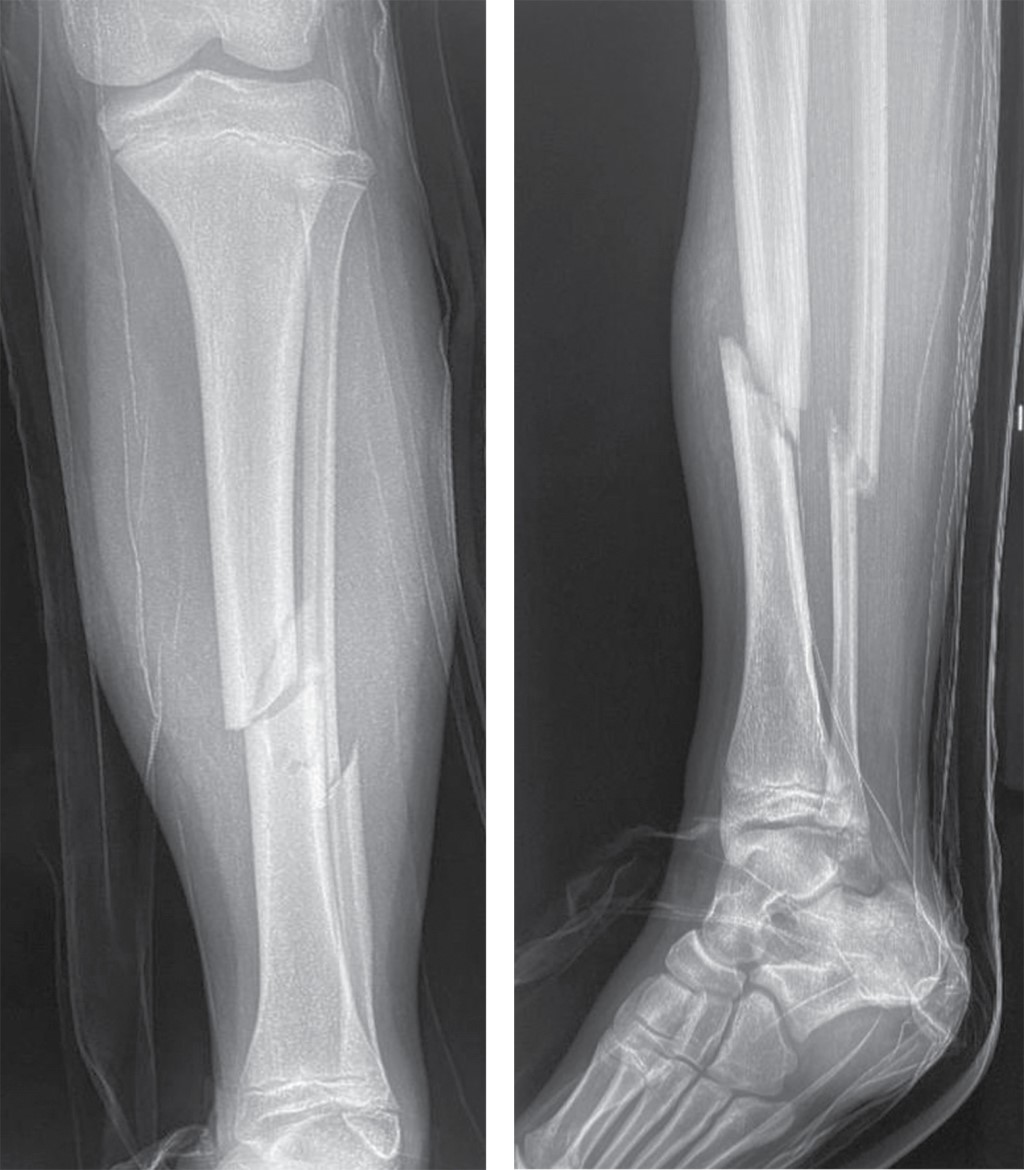

Figure 2